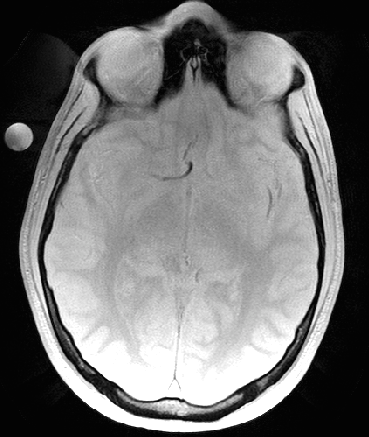

Refer to caption

(a) Magnitude image

(b) PPM map, Phi

(c) Corrected PPM map, 𝚽𝐡subscript𝚽𝐡\bf\Phi_{h}

(d) 𝚽𝐛subscript𝚽𝐛\bf\Phi_{b} field map

Figure 6: Background suppression of a ppm map with water and fat signal. (a): Magnitude of the first echo of a multi echo sequence. (b): PRF map estimation using ARMA technique.(c): Background suppressed PRF map. (d): Estimated background field map in ppm. The fat and water peak is aliased with 4.324.324.32 ppm due to the chosen echo spacing. the fat-water boundary. The labels 1 and 2 are water and fat ROIs that are used to determine the CNR gain of the method.

An MFGRE sequence was used to collect using a 3T scanner (SIGNA; GE Healthcare Technologies, Waukesha, WI) 16 echoes with echo spacing of 1.816ms1.816𝑚𝑠1.816ms, TR=75ms𝑇𝑅75𝑚𝑠TR=75ms, Matrix 128×128128128128\times 128 and Pixel Bandwidth of 651.016Hz651.016𝐻𝑧651.016Hz. Figure 6 (a) illustrates the magnitude of the first echo of a slice through the pelvis. The multi echo data is processed pixel wise by the ARMA technique. The resulting PRF in ppm at each pixel is illustrated in Panel (b). The dark areas in panel (b) are subcutaneous lipid. Inhomogeneities of the PRF can be seen near the air inclusion in the middle and throughout the image, in particular in the lipid regions. The result of the background suppression technique is shown in Panel (c), which illustrates, that most of the background inhomogeneities have been removed. Note the fat-water ppm difference is about 1.16ppm1.16𝑝𝑝𝑚1.16ppm and not the expected shift of about 33.5ppm33.5𝑝𝑝𝑚3-3.5ppm. This is a consequence of aliasing introduced by the finite sampling in echo direction. If the aliasing is taken into account by adding the bandwidth of 4.3212ppm4.3212𝑝𝑝𝑚4.3212ppm, then the fat-water shift is 3ppm3𝑝𝑝𝑚3ppm as expected. The pixel wise difference of the images in Panels (b) and (c) is shown in Panel (d). Note that the estimated background field 𝚽𝐛subscript𝚽𝐛{\bf\Phi_{b}} is smooth in areas of transitions of fat and water. The map is not necessarily smooth in areas of low signal, however a correct estimation of the background in low signal areas is not a well-posed problem.